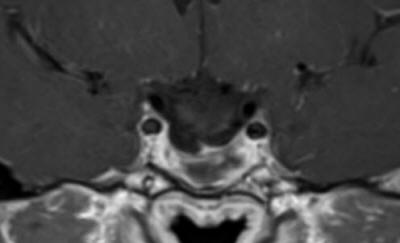

The patient was sent for thorough investigations and MRI cervical spine performed 04-September-2016 showed huge meningioma 33x12.7 mm intradurally pushing the spinal cord to the left. Spectroscopy was typical for meningioma and the mass was lacking fibers. There was and extension to the right C1-2 foramen reaching the vertebral artery pushing it anterior.

Fig-14: The meningioma in different sections and sequences.

Fig-20: Check MRI before extubation.

Fig-21: Check MRI before extubation,